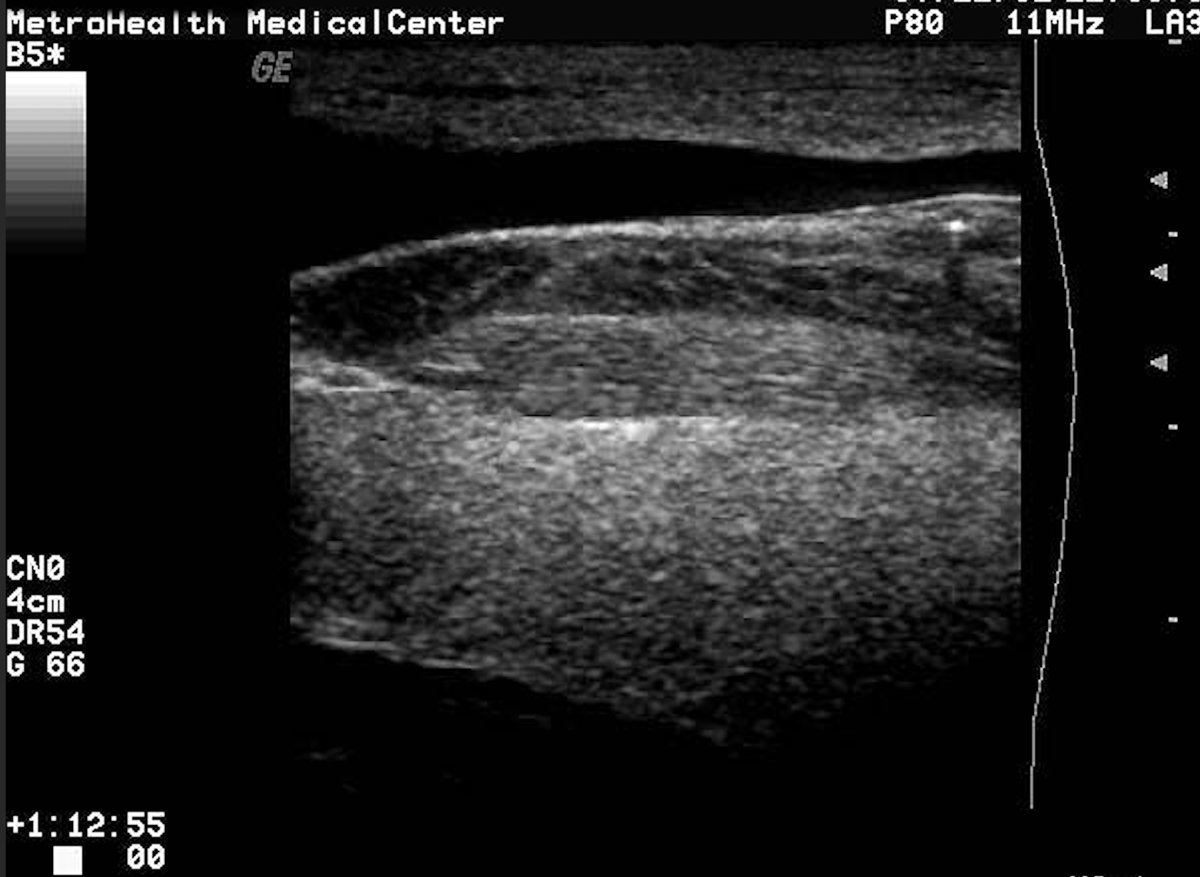

Retained wood splinter in heel with posterior shadowing seen. Injury happened one day ago. Standoff pad used.

Piece of bamboo broke off in arm 5 days ago. Seen at another facility. Xrays negative. Given Keflex and sent home. Now with increasing pain and early redness. Importance of POCUS for wood/vegetative FBs.